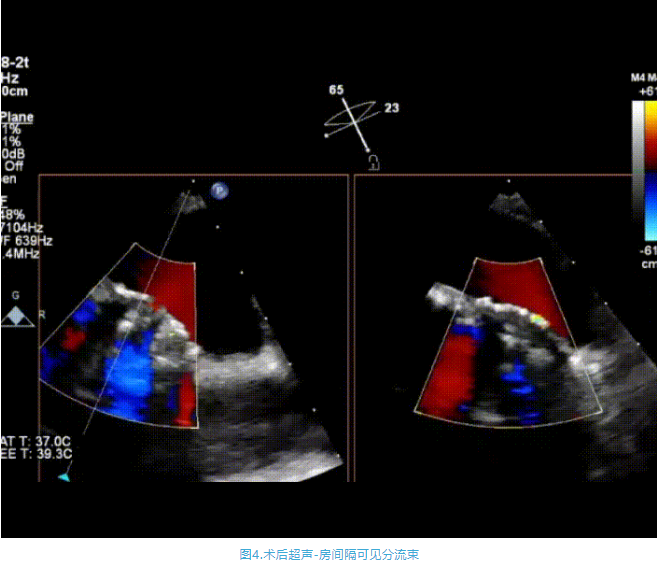

術(shù)中首先在局麻下穿刺股動(dòng)脈、股靜脈,完成心導(dǎo)管檢查評(píng)估后轉(zhuǎn)為全麻,在食道超聲引導(dǎo)下穿刺房間隔,穿刺成功后將加硬導(dǎo)絲送入左上肺靜脈建立軌道,根據(jù)患者病情行球囊預(yù)擴(kuò)張后植入6mm孔徑房間隔造孔支架,經(jīng)透視及食道超聲評(píng)估支架左右盤展開良好,夾持于房間隔兩側(cè),固定穩(wěn)定、位置良好,食道彩超顯示房水平右向左為主分流,分流孔直徑符合預(yù)期大小,心導(dǎo)管檢查評(píng)估達(dá)到預(yù)期效果,釋放造孔支架。術(shù)后12h患者下床活動(dòng),恢復(fù)順利,擬于近日完善術(shù)后評(píng)估后出院。